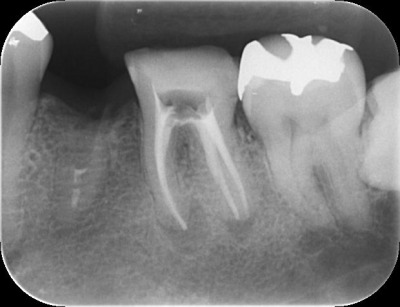

初診時のレントゲン写真では左下第一大臼歯、近心根根尖にレントゲン透過像が確認できます。

また、遠心根は根尖に透過像は認められませんが、適切な処置が施されているようには見えません。

- 初診時レントゲン写真